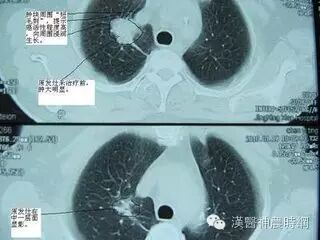

腺癌这种类型和吸烟关系最小,占肺原发肿瘤的40%。常位于肺的周边部,还累及胸膜并形成相关的疤痕圈和胸腔积液。周围型腺癌发生在和结核或梗死或其他损害相关的疤痕区的理论已经有很长时间了。疤痕癌的概念提示癌前病变上皮在疤痕区发生改变引起癌。然而一些研究者则提出疤痕继发于癌。

腺癌是腺上皮恶性肿瘤,可以有腺泡、乳头、细支气管肺泡或实性生长方式。它常伴有黏液产生,检测黏液需要特殊的染色,尤其在分化差的肿瘤。黏液的检测有时能够鉴别实性腺癌与其他形态表现一样的大细胞癌。